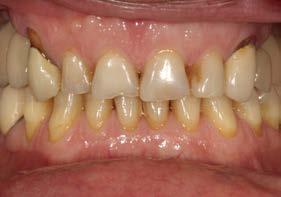

Explantación atraumática y recambio de implantes mal posicionados y afectados por periimplantitis sumado a la utilización de implantes estrechos y cortos. Enfoque mínimamente invasivo de un caso de atrofia ósea moderada

42 | INVESTIGACIÓN CLÍNICA